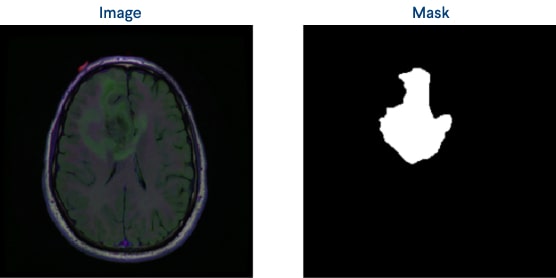

Figure 3: An original image and a mask example

We were provided with CT images in .tif format, each containing three channels: pre-contrast, FLAIR, and post-contrast. In addition, an image-mask pair was available for each image. To extract data from these images, we performed radiomics feature extraction using Pyradiomics 3 packages’ Radiomics Feature Extraction method, which involved extracting 55 features for each channel. These features provide valuable information about the tumor's phenotype, heterogeneity, and other characteristics.